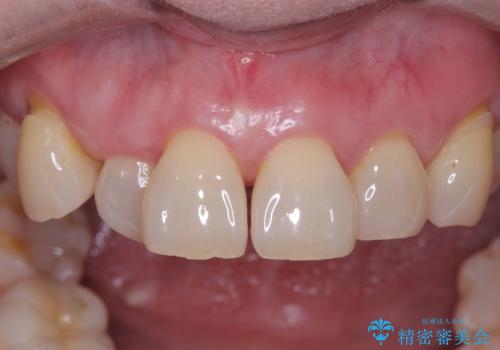

[ セラミック治療 ] 前歯の見た目を改善したい

![[ セラミック治療 ] 前歯の見た目を改善したいの症例 治療前](https://seimitsushinbi.jp/wp/wp-content/uploads/2025/10/IMG_9990-2-500x350.jpg?v=1761816440)